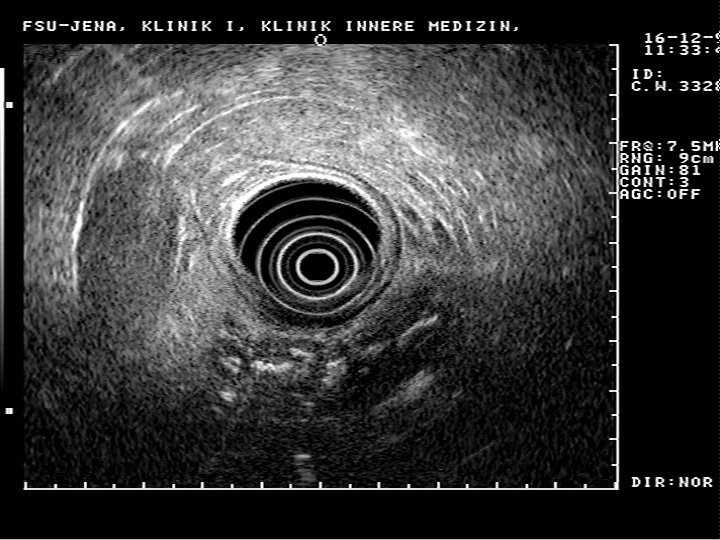

1. l’échographie abdominale: - peut déceler une tumeur pancréatique hypoéchogène supérieure à 2 cm - peut montrer une dilatation des voies biliaires, de la vésicule ou une dilatation du Wirsung - déceler: ascite, ganglions, métastases 2. L’écho-endoscopie: - détecte des lésions inférieures à 2 cm - précise l’extension loco-régionale: envahissement des vaisseaux porte ou mésentérique - permet une cyto-ponction (qui n’a de valeur que si positive) 3. TDM et IRM +++: - détecte les masses hypodenses focales ou diffuses - et les signes indirects +++: dilatation biliaire, du Wirsung, atrophie parenchymateuse d’amont

1. La compression de la voie biliaire: - ictère rétentionnel progressif, sans fièvre - tests biologique de cholestase - l’écho + TDM montre une dilatation de la voie biliaire principale et intra-hépatique, ainsi que le pseudo-kyste - l’écho-endoscopie précise la sténose régulière du bas cholédoque - la CPRE réalisée en pré-opératoire montre la hauteur de la sténose